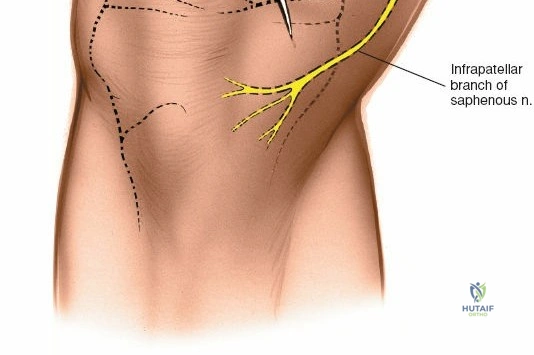

- Saphenous Nerve and Vein: Careful dissection is paramount to identify and protect the infrapatellar branch of the saphenous nerve and the greater saphenous vein, which lie within the subcutaneous fat layer. Retract them carefully.

- Nerve Injury:

- Incidence: <1%. Primarily involving the infrapatellar branch of the saphenous nerve, causing paresthesia, numbness, or neuropathic pain in the anteromedial knee.

- Management: Usually temporary. Neuropathic pain may be managed with medications. Rarely, neuroma formation may require surgical excision.